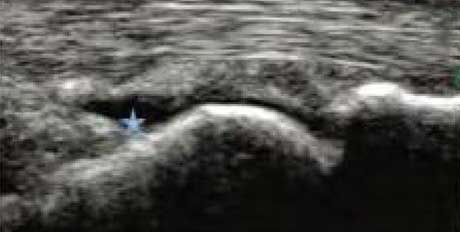

3、准确判断关节积液增加,精准判定RA严重程度

类风湿关节滑膜炎症会导致滑液渗出不断增多,形成关节腔积液。肌骨超声最少可发现1ml的积液,能对关节腔积液量及位置准确定位,通过检测判定关节腔内液性边界清楚的无回声区、细点状回声或细微的低回声条纹,判断其宽度和深度衡量积液量的多少,进而评估RA的严重程度。

Ⅰ级微量积液

滑膜囊内见前后径3.55mm液性暗区,呈椭圆形

Ⅱ级较多量积液

暗区内有团状高回声,可见深度达6.46mm液性暗区

Ⅲ级大量积液

关节囊扩张,可见大范围液性暗区,髌上囊积液深度达11.2mm